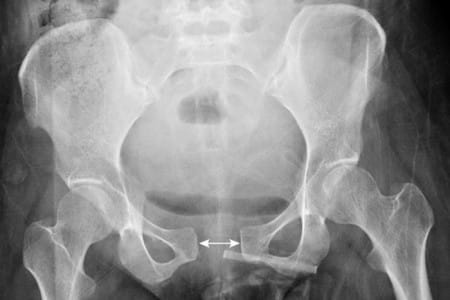

- Рентгенография.

Основным методом исследования, который является лакмусовой бумажкой в диагностике послеродовых травм и поражений связочного аппарата таза, остается рентгенография. Именно благодаря ей можно поставить такие диагнозы, как «симфизит», «разрыв сочленений», «перелом и вывих копчика», «сакроилеит».

По рентгенологическим данным выделяют 3 стадии, или степени тяжести, симфизита:

- I стадия – расстояние между тазовыми костями от 0,5 см до 1 см;

- II стадия – от 1 см до 1,9 см;

- III стадия – больше 2 см.

При увеличении расстояния более 2-3 см стоит задумываться о разрыве лонного сочленения.